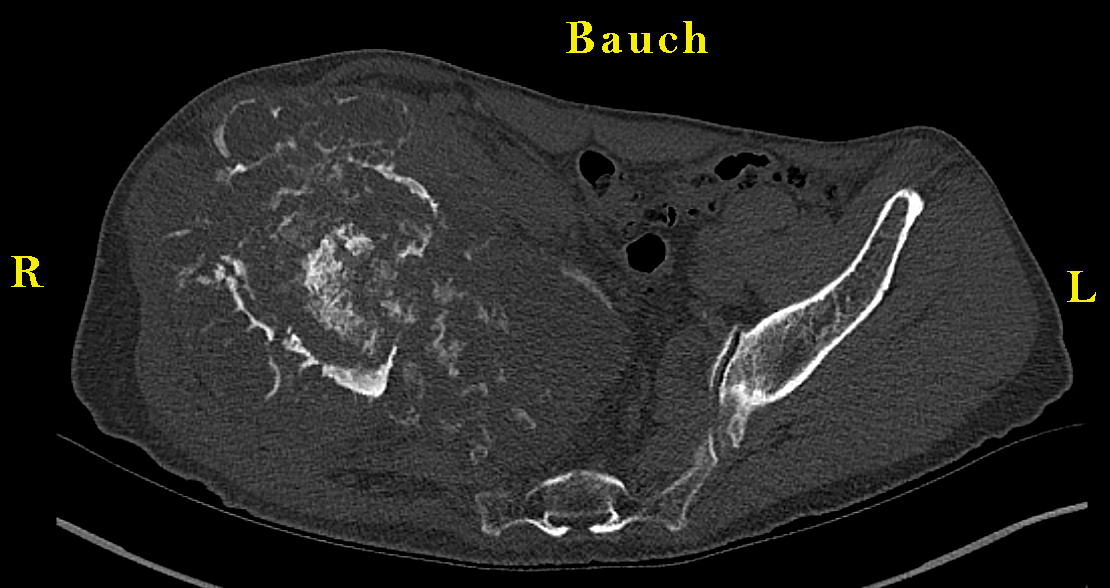

| Hirslanden Radiologie Bern, 24.4.2023, Raz, Ueli *06.01.1957 "MR und CT Becken sowie Rx Beckenübersicht vom 24.4.2023 Klinische Angaben, Fragestellung Morbus Ollier. Status nach sekundärem Sarkom der linken Schulter. 1. Diagnose 2002. Aktuell Befundprogress rechtes Os ilium DD: Sekundäres Chondrosarkom. Verlauf? Malignitätshinweise? Befund Die nachfolgenden Ausführungen beziehen sich sowohl auf die MRT, die Nativ-CT des Beckens wie auch die konventionelle Beckenübersicht. Die Beurteilung wird der Übersicht halber in 5 Sektoren aufgeteilt: Hemipelvis rechts, proximaler Femur rechts, Hemipelvis links, proximaler Femur links und das Sakrum. Hemipelvis rechts: Voraufnahmen zum Vergleich liegen aktuell im PACS nicht vor, der Patient hat auch keine Aufnahmen mitgebracht. Allerdings findet sich im PACS eine Beckenübersicht vom 10.4.18, wo im Os ilium rechts noch kein Enchondrom identifiziert werden konnte. Die nachfolgend beschriebene voluminöse polylobulierte Läsion mit Zentrum in der Fossa iliaca des Os ilium rechts zeigt in verschiedener Hinsicht eindeutige Hinweise auf eine maligne Entartung bzw. dürfte es sich bei der Läsion anhand der bildmorphologischen Kriterien und klinischen Angaben (Morbus Ollier) um ein Chondrosarkom handeln. Die entscheidenden Faktoren dieser Gewichtung liegen an der vollständigen Destruktion grosser Teile des Os iliums inklusive des Cortex, der erheblichen extraossären Weichteilausbreitung, der lokoregionären nachfolgend beschriebenen Weichteilinfiltrationen und den Periostreaktionen. Die Läsion ist polylobuliert und insgesamt etwas unregelmässig konfiguriert und zeigt auf dem axialen Bildmaterial Durchmesser von bis 17,5 x 12 cm und auf den koronaren Bildern Durchmesser von 15 x 9,5 cm. Sagittal misst man Durchmesser von 15,5 x 10 cm. Das konventionelle Übersichtsbild und dann vor allem die CT zeigt eine erhebliche ossäre Destruktion infolge Osteolysen, die in der Fossa iliaca ihr Zentrum haben und sich in alle Richtungen ausdehnen. Die Knochendestruktionen betreffen insbesondere auch den ossären Kortex. Die Osteolysen reichen bis in den vorderen acetabulären Pfeiler und erstrecken sich von hier in den vorderen Schambeinast rechts, wobei aber die parasymphysäre Region nicht betroffen ist. Weitreichende Osteolyse im dorsalen acetabulären Pfeiler und daran anschliessend im gesamten Os ischiadicum und auch am Übergang zum unteren Schambeinast - an dieser Lokalisation ist die Zusammenschau mit der MRT hilfreich, da die kleinen Lysen in der CT nicht so eindeutig sind. ln der MRT zeigt die Läsion die für die Tumormorphologie typische chondroide Hyperintensität in den fettsaturierten T2-gewichteten Sequenzen. Typische komplementäre Hypointensität in der T1-Gewichtung. Die polylobulierte konfigurierte mineralisierte chondroide Matrix des Tumors ist vor allem in der Peripherie gut zu erkennen. Diese zeigt und in der MRT ein hypointenses Signal und präsentiert sich wegen der hohen Dichte in der CT als lobulierte Verkalkung. Nach i.v.- Kontrastmittelapplikation wird eine grosse zentrale Nekrose der Läsionen sichtbar, die keine oder kaum Kontrastmittel aufnimmt; die vitalen Anteile der Läsion zeigen hingegen ein massives Enhancement. Die Weichteilausdehnung lässt sich hier am besten einschätzen (z.B. Serie 14). Es besteht ein relevante Tumorausdehnung sowohl nach aussen in Richtung Glutealmuskulatur wie auch nach innen in Richtung Pelvis. Von der Glutealmuskulatur betroffen bzw. infiltriert ist der Musculus gluteus medius und minimus; der Musculus glutaeus maximus dürrfte kaum betroffen. Aufgrund der Tumorausdehnung muss man von einer lnfiltration sämtlicher Muskelansätze und / oder Muskeln ausgehen, die am Os ilium ihren Ursprung haben. Mit eingeschlossen sind hier Crista iliaca, die Spina iliaca anterior superior und anterior inferior sowie das Os ischiadicum und der Übergang zum unteren und oberen Schambeinast rechts. Die Tumorausdehnung in Richtung Pelvis fülhrt zu einer breitbasigen Infiltration des Musculus iliacus. Der Musculus psoas anterior davon ist im Pelvis stark nach anterior verdrängt, ausgespannt und zeigt in der Übergangszone ein pathologisches Enhancement - man muss hier von einer zumindest punktuellen Infiltration ausgehen. Die Tumorausdehnung in Richtung Pelvis beansprucht volumenmässig fast die Hälfte des grossen Beckens und mindestens die Hälfte des kleinen Beckens. Die A. und V. iliaka communis und iliaca externa sind stark nach innen abgedrängt, erscheinen aber nicht infiltriert. Hingegen muss von einer Infiltration der Arteria iliaca interna rechts ausgegangen werden. Erhebliche Verdrängung der Harnblase zur linken Seite; das Organ scheint nicht infiltriert. Ebenso gilt dies für die Prostata, das Rektum und das Colon sigmoideum, das multiple Divertikel erkennen lässt. Proximaler Femur rechts: Das Caput femoris rechts ist zirkulär von Tumorgewebe umgeben; in diesem Sinne ist das Acetabulum inexistent. Dies hat auch dazu geführt, dass ein erheblicher Hochstand des Femurs rechts besteht infolge eines breitbasigen Einbruchs des Acetabulums, das mehr oder weniger vollständig lysiert ist. Der Hochstand gegenüber dem Femurkopf links beträgt über 2 cm. Computertomographisch findet sich im Caput femoris rechts eine umschriebene Osteolyse und zwar im apikoposterioren Anteil. An dieser Lokalisation ist in der MRT nach i.v.- Kontrastmittelapplikation ein signifikantes Enhancement zu erkennen. Diese Befundkonstellation ist höchst verdächtig auf eine Infiltration des Feinurkopfes. Daneben sind keine Osteolysen zu erkennen; das Caput und Collum femoris zeigt aber inhomogene Knochenmarksödeme die assoziiert sind mit einem inhomogenen Enhancement des Knochenmarks, das bis zur Regio intertrochanterica reicht. Entlang diesem Verlauf sind mehrere grobschollige Verkalkungsherde in der spongiösen Matrix zu erkennen. Anzufügen bleibt hier noch, dass das Beckenübärsichtsbild vom 10.04.18 keine Coxarthrose rechts oder links zeigte also - es höchst unwahrscheinlich oder ausgeschlossen ist dass diese Pathologien in Zusammenhang mit einer Arthrose stehen. Aufgrund der Gesamtpräsentation muss man meiner Sicht nach von einer lnfiltration des Femurkopfes ausgehen. Eine aseptische Osteonekrose erscheint als Differenzialdiagnose möglich aber unwahrscheinlich (Ausdehnung zu gross, keine subchondralen Einbrüche der Kompakta erkennbar). |

| Hemipelvis und proximaler Femur links: Das Hemipelvis links zeigt ebenso einzelne osteolytische Herde, die aber computertomographisch vor allem dadurch imponieren, dass sie unregelmässig verkalkte Matrix aufweisen, vorzugsweise in der Peripherie. An keiner Lokalisation ist dabei der Kortex des lliums signifikant ausgedünnt oder pelottiert d.h. bei diesen Befunden muss es sich in erster Linie um Enchondrome in Zusammenhang mit dem Morbus Ollier handeln. Diese liegen hauptsächlich im dorsalen Anteil des lliums. Eine entsprechende typische Präsentation findet sich in Analogie dazu auch in der MRT. Sekundär haben die Befunde punktuell zu Arthrosen im lliosakralgelenk Gelenk geführt (über asymmetrische Gelenkverhältnisse) Absolut unauffällige Präsentation des Caput und Collum femoris links. Kein Tumorbefall. Os sacrum beidseits: Das Sakrum zeigt beidseits keine Osteolysen, In der MRT bestehen aber suspekte Auffälligkeiten an der anteroinferioren Zirkumferenz der Massa lateralis rechts, dieses Segment, das gerade dem Foramen ischiadicum gegenüber liegt. Hier findet sich eine Signalminderung des Knochenmarks in der T1-Gewichtung und ein korrelierendes Ödem und ein KM-Enhancement. Gleichzeitig reicht das Osteosarkom breitbasig an diesen Teil des Sakrums heran, da das gesamte benachbarte Foramen ischiadicum infiltriert ist - eine Infiltration dieses Sakrumsegmentes ist deshalb sehr wahrscheinlich. Eine breitbasige lnfiltration des Plexus ilosakralis rechts erscheint hingegen wenig wahrscheinlich. Keine Infiltration des linksseitigen Sakrums. Keine Infiltration des Corpus vedebrae LWK 5. Beurteilung: Riesige polylobulierte Tumormasse, die sich ausgehend von der Fossa ischiadica in alle Richtungen ausbreitet. Aufgrund der dargelegten Kriterien und der Gesamtpräsentation muss es sich hier um ein lokal infiltrierendes Osteosarkom handeln. lm Bezug auf die Grösse, Gesamtausdehnung und die Infiltration ossären Strukturen, benachbarter Weichteile und Organe siehe Ausführungen im Text. Speziell zu nennen bleibt hier, dass mit grosser Wahrscheinlichkeit eine Ausdehnung per continuitatem ins Caput und Collum femoris rechts besteht und ebenso eine punktuelle Infiltration der Massa lateralis des Os sacrum rechts anzunehmen ist." |